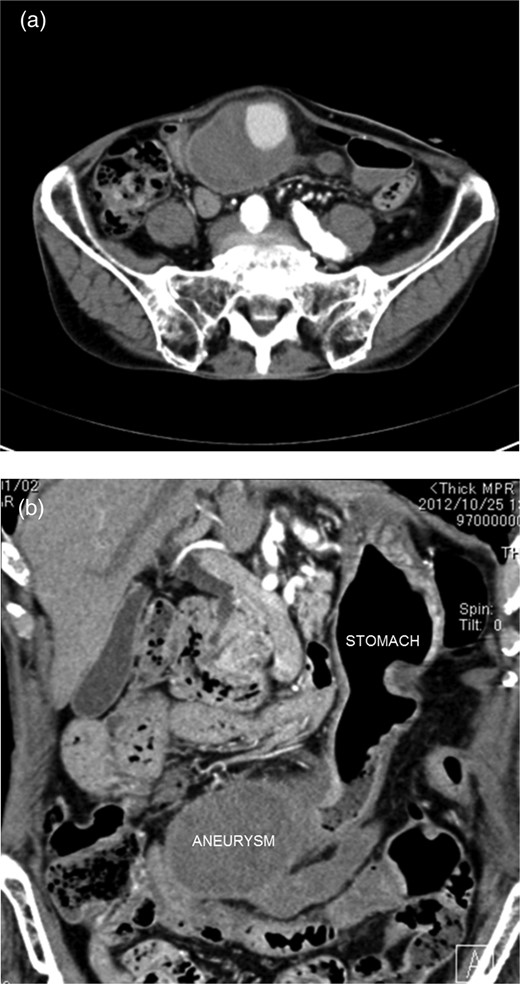

An 85-year-old man complaining of vague abdominal discomfort was admitted to our hospital. He had a medical history of arterial hypertension. Upon admission, his general status was stable. A pulsatile 8 × 7-cm mass in the right upper abdomen was noticed on clinical examination. Abdominal arterial aneurysm was diagnosed, and imaging studies were performed. Abdominal ultrasonography showed that the mass was present on the border of the greater curvature of the stomach, and blood flow was observed inside it (Fig. 1a and b). The mass was not connected to the abdominal artery. Computed tomography of the abdomen showed a huge arterial aneurysm in the right gastroepiploic artery, and the left gastroepiploic artery was meandering and expanding (Fig. 2a and b). There was no bleeding or ascites in abdominal cavity. Accordingly, an image diagnosis of GEAA was made. Because of the huge size of the aneurysm and the predicted high risk of perforation, surgical intervention was planned.

(a) Abdominal ultrasonography showed that the mass was present on the border of the greater curvature of the stomach. (b) Blood flow was observed inside the mass.

Computed tomography of the abdomen showed a huge arterial aneurysm in the right gastroepiploic artery.